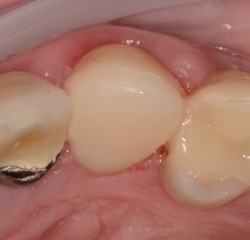

- Cas 3 : 1 molaire inférieure - 1 séance de 75 minutes